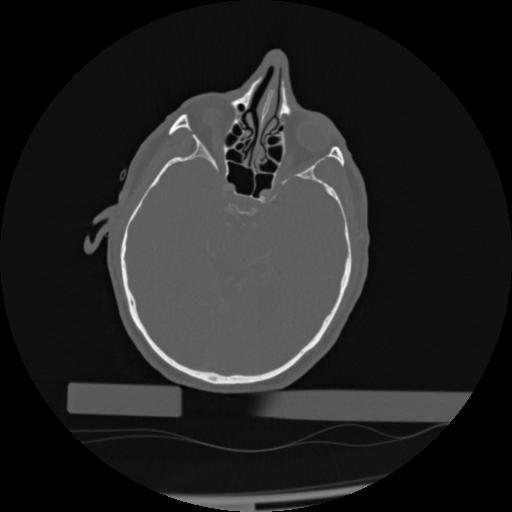

22 ANGIO,CE,Vol,0.5,ANGIO,,